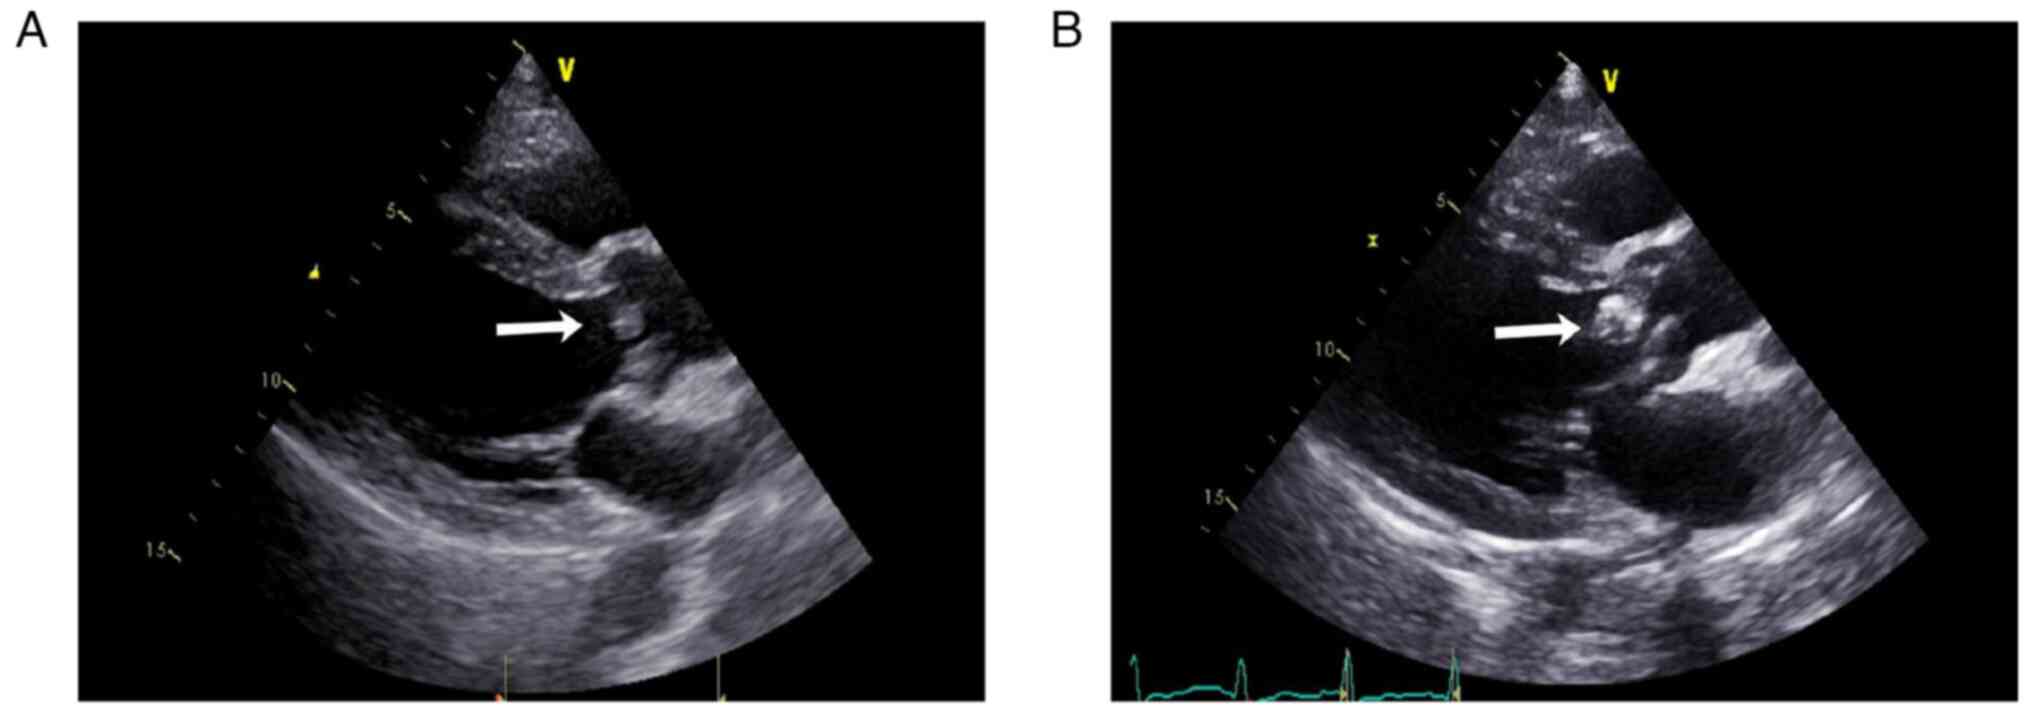

The patient presented with fatigue and anorexia 1 year beforehand (August 2016). Urinalysis revealed 50-70 deformed red blood cells (normal range, 0-3) per high-power field. Urinary protein excretion was 0.51 (normal range, <0.15) g/day and the serum albumin concentration was 33.2 (normal range, 40-55) g/l. The serum creatinine (SCr) concentration was 209 (normal range, 44-133) µmol/l. The white blood cell count of the patient was 6.2 (normal range, 3.5-9.5) x109/l and the neutrophil count was 3.6 (normal range, 1.8-6.3) x109/l. C-reactive protein (CRP) was 13.4 (normal range, 0-8) mg/l, and the erythrocyte sedimentation rate (ESR) was 60 (normal range, 0-15) mm/h. The serum c-ANCA concentration was 1:32 (serum:diluent; normal range, negative), and the anti-PR3 antibody concentration was >200 (normal range, <20) RU/ml. The rheumatoid factor (RF) concentration was 155 (normal range, <30) IU/ml, and the circulating immune complex (CIC) concentration was 147.1 (normal range, <20) RU/ml. The IgG concentration was 35.1 (normal range, 7.2-16.8) g/l, and the complement C3 concentration was 0.507 (normal range, 0.6-1.5) g/l. Antinuclear antibody (IIF) and anti-glomerular basement membrane (GBM) antibody were negative. Hepatitis B, hepatitis C, syphilis and HIV screening were negative. Kidney pathology revealed focal proliferative necrotizing glomerulonephritis accompanied by crescent formation and immune complex-mediated glomerulonephritis (Fig. 1A). Immunofluorescence staining of frozen tissues was performed to detect IgG (Fig. 1Aa) and C3 (Fig. 1Ab), and was evaluated under a fluorescence microscope as described previously (7). Kidney biopsy specimens were fixed in 4% buffered formaldehyde at 4˚C for at least 4 h for light microscopy as described previously (8). Paraffin-embedded kidney sections (3 µm) were used for histologic staining, including periodic acid-silver methenamine and Masson trichrome staining (Fig. 1Ac) and periodic acid-Schiff staining (Fig. 1Ad) as described previously (7). Approximately 1 cm3 of cortical renal tissue was taken, fixed with 3% glutaraldehyde, postfixed in 1% osmium acid, dehydrated with a graded acetone series and then embedded in epoxy resin. Tissues were then sliced into 80-nm ultrathin sections and analyzed using the JEM-1400 transmission electron microscope (Fig. 1Ae and Af) as described previously (9). Echocardiography revealed no vegetation (Fig. 2A). The patient was treated with a methylprednisolone pulse (500 mg/d x 3 days) two times, followed by prednisone 50 mg/d for ~1 month, combined with intravenous cyclophosphamide 0.6 g/month six times. After 1 month, the SCr concentration decreased to 136 µmol/l, anti-PR3 antibody level decreased to 154 RU/ml and the general condition of the patient improved, with a Barthel activities of daily living (ADL) index score of 100(10). Prednisone was gradually reduced to 20 mg/d and cyclophosphamide accumulated 3.6 g.

Figure 2

Cardiac ultrasonography of the patient. (A) At the time of disease onset, cardiac ultrasonography showed left ventricular symmetrical hypertrophy, moderate aortic regurgitation, aortic valve sclerosis/calcification (no aortic valve vegetation, arrow), mild aortic stenosis, mild mitral and tricuspid regurgitation and a normal left ventricular ejection fraction. (B) Approximately 1 year later, cardiac ultrasonography revealed aortic and mitral valve disorders, aortic valve vegetation (arrow), moderate to severe aortic regurgitation, mild aortic stenosis, severe mitral regurgitation, left atrium and left ventricular enlargement, left ventricular symmetrical hypertrophy, a normal left ventricular ejection fraction (62.3%), mild tricuspid regurgitation and elevated pulmonary systolic pressure.

The patient was positive for type II cryoglobulin. C3 was <0.058 g/l, C4 was <0.032 g/l and C1q was 116.5 (normal range, 159-223) mg/l. ANCA, antinuclear antibody (IIF), anti-β2-glycoprotein 1 antibody (ELISA), anticardiolipin antibody (ELISA) and anti-GBM antibody were negative. The IgG, IgA and IgM levels were within the normal range. The ESR was 21 mm/h. Infection screening, which included bacteria, fungi and viruses and was performed on serology and specimens, including sputum, stool and urine, was negative. Due to the long-term use of steroids and immunosuppressants and the high leukocyte, neutrophil counts and PCT, the patient received 1.5 g of intravenous cefoperazone-sulbactam every 12 h. Blood culture (after intravenous cefoperazone-sulbactam at 1.5 g every 12 h for one week) was negative three times. Echocardiography (Fig. 2B) revealed vegetation on the aortic valve. The patient denied a history of intravenous illicit drug use. After careful questioning it was revealed that the patient had a history of tooth extraction without antibiotics 1 year prior.